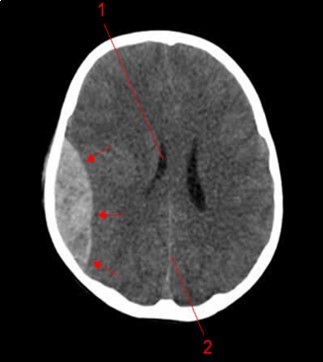

From the point of view of care, two (n=2) (10.52%) children received medical treatment compared to 17 (89.48%) children who received medical-surgical treatment. Neurosurgical treatment consisted of evacuation of the extra dural hematoma. This involved making a skin incision, trepanation (Figure 3 a), a preserved cranial bone flap, evacuation of the extra-dural haematoma (Figure 3 b), haemostasis either of the bone using bone wax or venous or arterial haemostasis by bipolar coagulation as appropriate, suspension of the dura mater (Figure 3 c), replacement of the bone flap (Figure 3 d) and finally suturing of the scalp in two planes. Figure 1, Figure 2, Figure 3.

Figure 1.Image of a brain CT scan without contrast, in a parenchymal window, axial view showing a right parietal extra dural hematoma associated with diffuse cerebral oedema, and subfalcorial brain schift